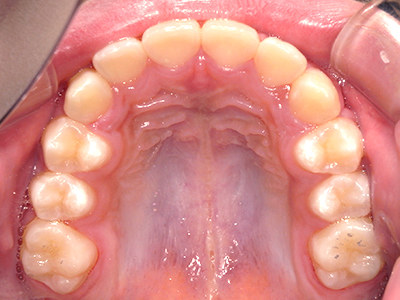

歯並びの相談に来られるお子様は、口呼吸をしているケースが多く、これが歯並びに大きな影響を与えています。

- 口呼吸をしている

↓ - 舌の位置が悪くなる

↓ - 頬の圧力が上の歯列にかかりやすくなる

↓ - 上あごが狭くなる

↓ - 下あごが狭くなる・下あごの位置が悪くなる

↓ - さまざまな不正咬合が生じる

ないき歯科クリニックでは、上あごの成長不足を補い、鼻呼吸を獲得しつつ歯列を整え、将来のお口をより健康な状態にすることをゴールに定める矯正治療をおこなっています。